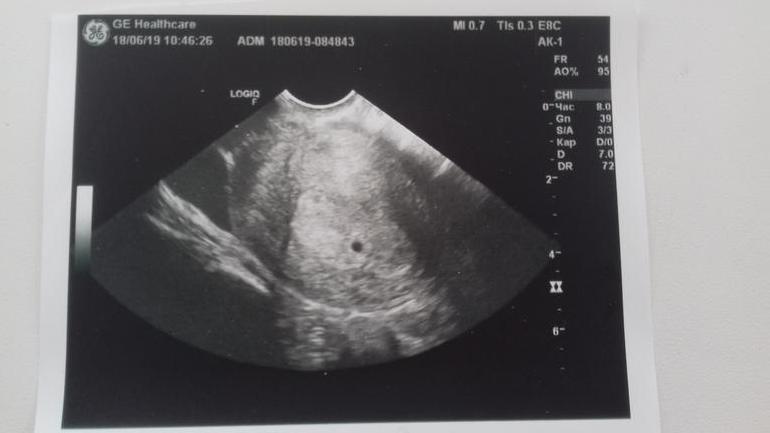

Наша 5 неделька

Сегодня (18.06) была на УЗИ. Врач сказала, что у меня эмбриончик на 3 неделе по развитию 😊, по месячных это пятая недельку. К врачу поехала потому , что болело в правом боку. И упала БТ с 37.2 до 36.9 😕 Я уже на придумывали себе кучу всего.